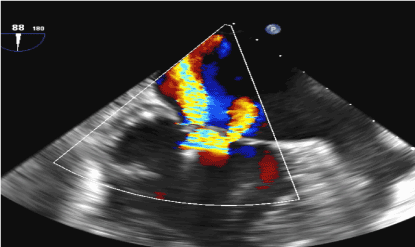

Figure 3. Shows a color Doppler of a cross sectional section of the Mitral valve with the Mitraclip in place. The picture shows severe MR on the color doppler